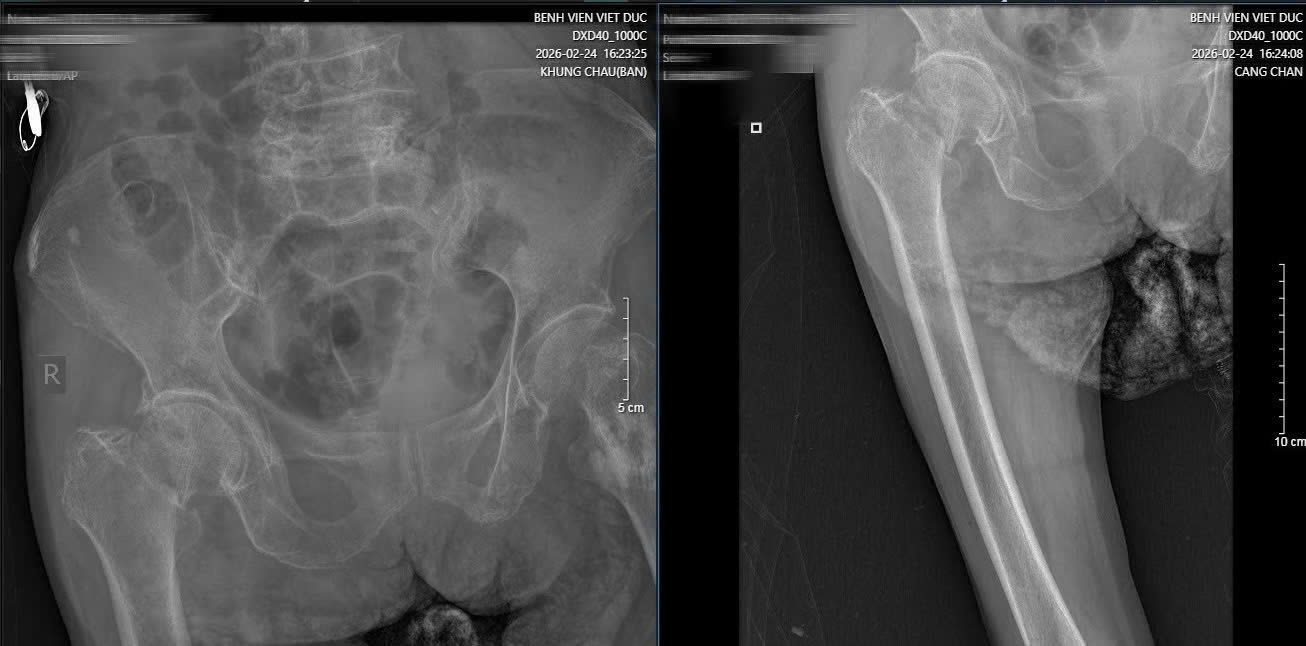

Hình ảnh phim X-quang cụ bà 89 tuổi nhập viện gãy cổ xương đùi phải và hình ảnh chụp CT ổ bụng và phát hiện khối u ruột non gây lồng ruột.

Ngoài ra, cụ còn mắc nhiều bệnh lý nền như vẹo cột sống, xẹp và trượt đốt sống thắt lưng, khiến việc điều trị trở nên khó khăn.